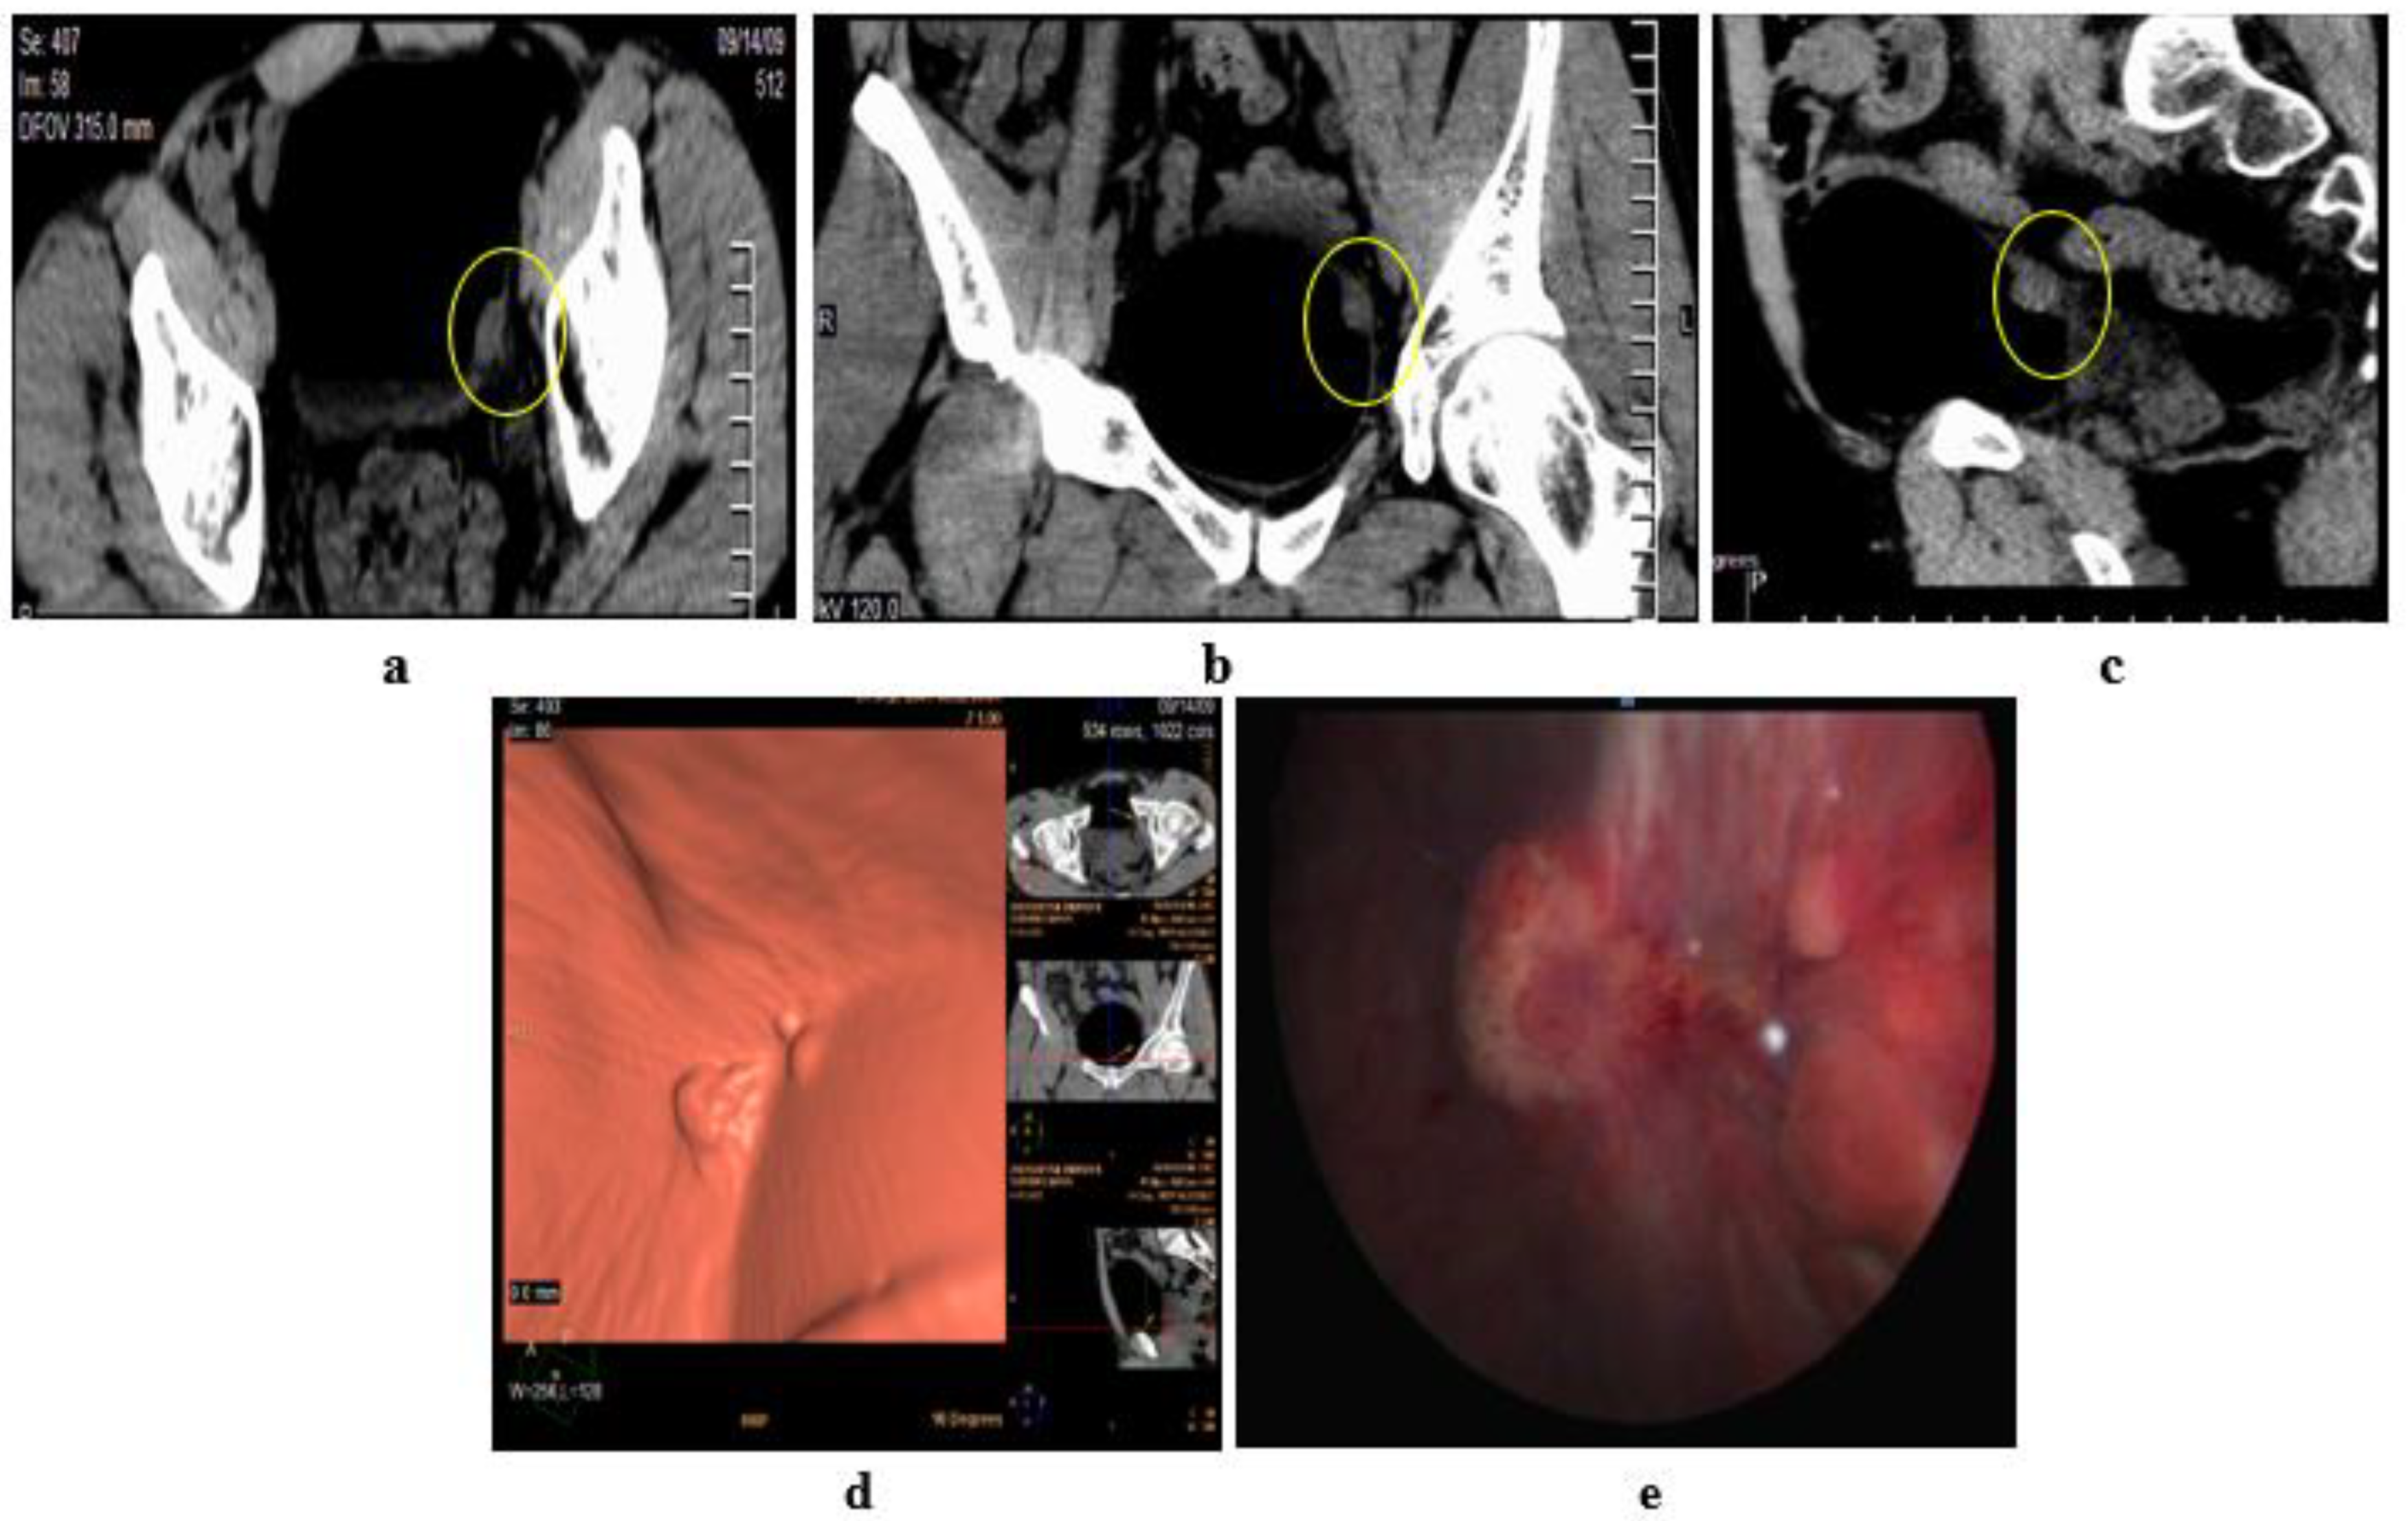

2.5. Virtual Cystoscopy (VC)

- Noncontrast CT of the pelvis subsequent to air/CO2 filling via a urethral catheter, then virtual reconstruction of images.

- Delayed phase of MDCT urography, then CT virtual cystoscopy reconstruction.